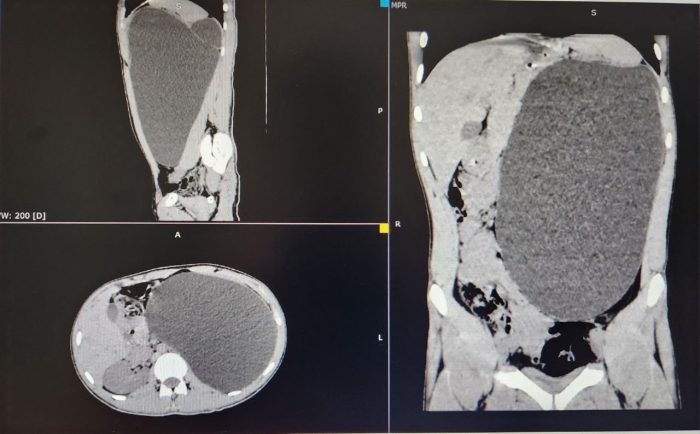

«Такое бывает либо при огромных опухолях, либо при гидронефрозе IV степени, когда почка превращается в гигантский мешок, заполненный мочой. У пациента был второй вариант. Почка достигла размеров пятилитровой бутылки! Она занимала почти весь объем живота и давила на все соседние органы. Это была настоящая «бомба замедленного действия»: любая травма, случайный удар в живот — и мешок мог разорваться внутри», — рассказали сегодня в ДГКБ №1.

Такому результату медосмотра были удивлены все. Ведь молодой человек ни на что не жаловался, состояние его почки не вызывало никаких побочек. Родители сначала даже не поверили и усомнились в необходимости операции. Но после разъяснений врачей согласились. Юноше провели лапароскопию. Через четыре небольших прокола откачали всю жидкость, а затем «ювелирно» отделили капсулу от тканей и наложили клипсы на сосуды. Фактически хирурги «достали пятилитровую бутылку через замочную скважину».